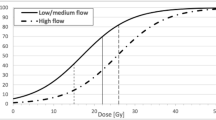

The patient response rate was 32.4 %. Thirty-five patients (14 male, 21 female) met the inclusion criteria and were included in the study; mean age of included subjects was 49.4 ± 12.4 years (median, 46 years). The AVMs were irradiated 16.6 ± 3.5 years (median, 17 years, range, 10–22 years) prior; AVM obliteration proven by DSA performed 13 ± 4 years (median, 13 years, range, 4–21 years) prior. Thirty-seven AVM nidi in 35 subjects were irradiated (two patients with two AVMs). AVMs were graded according to the Spetzler–Martin AVM classification [7] as Grade I in five, Grade II in 21, Grade III in eight, and Grade IV in three cases. The mean volume of the irradiated nidi was 3.41 ± 3.27 cc (median, 2.60 cc). Eleven AVM nidi were irradiated twice and 1 AVM was irradiated three times. The maximum dose of the first irradiation was 43.5 ± 7 Gy (median, 44 Gy, range, 34–54 Gy) with a margin dose of 21.7 ± 3.6 Gy (median, 22 Gy, range, 17–27 Gy). Eleven AVMs were secondarily irradiated with a maximum dose of 38.5 ± 7 Gy (median, 40 Gy, range, 28–46 Gy) and a margin dose of 19.2 ± 3.5 Gy (median, 20 Gy, range, 15–25 Gy). One AVM was irradiated a third time by a maximum dose of 44 Gy and a margin dose of 22 Gy.

Radiosurgery is a very successful minimally invasive treatment for brain AVM, with AVM obliteration occurring in more than in 90 % of treated cases [6]. The disadvantage of this method is the risk of re-bleeding until complete obliteration, as well as possible acute and subacute complications of GK treatment such as postirradiative edema [6]. However, there is also risk of delayed complications due to radiosurgical injury [8]. Radiation injury depends on numerous factors, of which the dose and the volume of irradiated tissue are the most important [9]. However, it is well known that the degree of radiographic changes is extremely variable and unpredictable [10]. It is influenced by the type of tissue treated, by the location of the lesion, as well as by individual sensitivity to radiation injury. It is widely accepted that normal brain tissue is more vulnerable to radiation injury than brain tumors [11].

In the present study, 35 patients (with 37 AVMs) were included who were treated by radiosurgery 16.6 ± 3.5 years prior to study onset, with AVM obliteration proven 13 ± 4 years prior. We found only one case (2.7 %) of serious late post-irradiative complication; a large cystic mass with high protein content and an enhancing wall. This patient required open surgery. Cyst formation is a rare but well-documented complication following radiosurgery for AVM [12, 13]. Its prevalence varies according to published reports from 1.1 % [14] to 5.5 % [13]. The prevalence of cyst formation may be higher in unruptured AVMs, as normal perinidal brain parenchyma is more vulnerable to radiation than gliosis after hemorrhage [14]. However, in the present case, symptomatic bleeding was present before GK radiosurgery. In a previous study by Izawa et al., predisposing factors for cyst formation included a large nidus volume, a high maximum dose, lobar localization, and complete AVM obliteration [15]. Delay from radiosurgery to cystic formation ranged from several months to many years. In the present case, GK radiosurgery was performed 21 years prior and AVM obliteration was proven 20 years prior to the study.

In the present study, we found that most obliterated nidi (28 of 37 nidi; 76 %) still clearly enhanced after intravenous gadolinium contrast administration, 16.6 ± 3.5 years after GK radiosurgery. This is in agreement with a similar study conducted by Kihlstrom et al., where 61 % of obliterated nidi enhanced after contrast administration [17]. They examined 18 patients with AVMs, who were treated with GK and in whom MRI was obtained a mean of 14 years after treatment and 10 years after confirmed AVM obliteration [17]. Postgadolinium enhancement in the site of AVM nidus is explainable by histological findings that were gained in a surgically treated patient who was discussed above. Histological evaluations showed signs of AVM vascular channel recanalization. This may explain the enhancement detected in the AVM nidus site, however it does not indicate the presence of an arteriovenous shunt, which was clearly excluded by DSA. Histology also showed newly formed vascular structures with iron deposits in their walls. These findings correspond with neo-angiogenesis and damage to the walls of newly formed vessels. Vascular injury, damage to the blood–brain barrier, vasogenic edema, and neo-angiogenesis are well-known effects of radiosurgery. Neovascularization has been described after radiosurgery for cavernous malformations [18] as well as radiosurgery in hippocampal sclerosis [8].

When we compared enhancing and non-enhancing nidi, we found that later enhancing nidi were significantly larger than non-enhancing at time of radiosurgery (4.39 ± 3.35 cc vs. 0.88 ± 0.79 cc, p = 0.004). However, enhancement was not influenced by total radiation dose, patient age, or duration since GK radiosurgery. We also did not find any statistical differences between postgadolinium nidi enhancement in subgroups AVM nidi irradiated once and more than once (two or three times). We found that nidi larger than 5.00 cc were associated with significantly less pre-treatment hemorrhage (12.5 % nidi) as opposed to nidi smaller than 5.00 cc (54.2 %). Similar findings have been described previously [6, 19, 20].